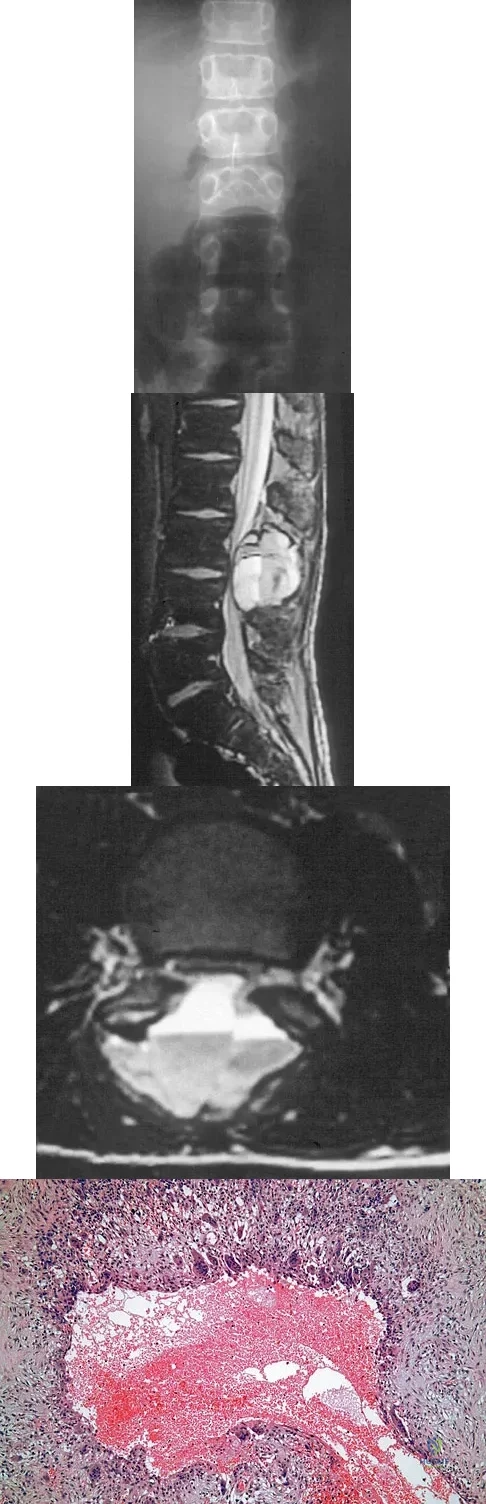

An 8-year-old boy is diagnosed with acute onset cauda equina syndrome. A radiograph, MRI scans, and a biopsy specimen are shown in Figures 57a through 57d. What is the most appropriate treatment?

Explanation